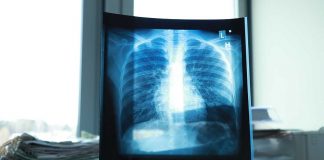

La enfermedad pulmonar obstructiva crónica (EPOC) es un síndrome clínico funcional en el que se incluyen pacientes con una limitación crónica al flujo aéreo...